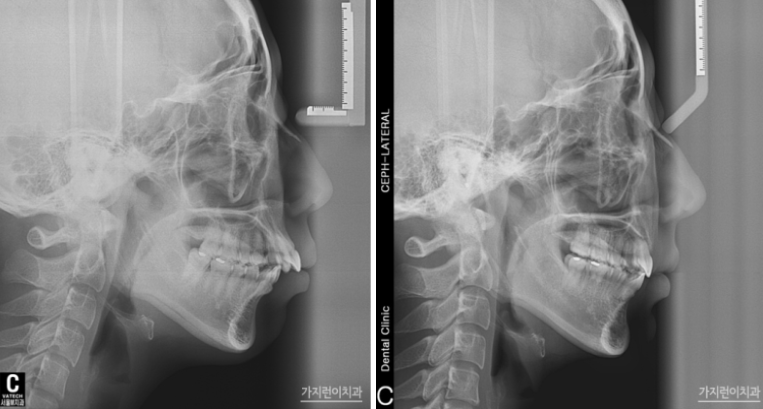

엑스레이 사진을 통해 확인할 수 있는 안모 변화도 눈에 띄는데요. 24개월이 소요된 교정기간 동안 장치는 티 나지 않으면서 교정을 완성할 수 있었기에 환자분의 만족도도 높은 편이었습니다. 탄댐설측교정 후에는 자연스럽게 입을 다물 수 있어 자연스레 미소를 머금던 모습이 기억나는데요. 티 나지 않는 직장인 교정으로 속 앓이 없이 성공적인 교정을 해보고 싶다면 본원을 방문해 탄댐설측교정 상담을 받아보시기 바랍니다.